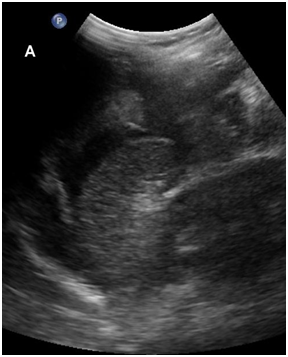

On examination, the patient’s temperature was 36.8 0C, blood pressure was 78/55mmHg, heart rate was 115 beats per minute. There were signs of acute abdomen with diffuse tenderness noted over the abdomen with guarding. On speculum examination, the cervical os was closed and there was no per vaginal bleeding. The patient was stabilized and fluid resuscitation immediately commenced. Urgent blood investigations sent off showed a full blood count with hemoglobin of 10.4g/dL and a total white cell count of 21.9 x 109/L. Urgent sonographic imaging showed an intrauterine live fetus with fetal tachycardia and irregular heart rate. There was intra-peritoneal free fluid and blood clots seen, indicative of hemoperitoneum (Figure 1). The uterine myometrium appeared discontinuous at the fundus, suggestive of uterine rupture (Figure 2). An i-STAT finger print blood count subsequently done showed a hemoglobin level of 5.8g/dL and packed red blood cell transfusion was immediately commenced. The patient was sent to the women’s intensive care unit and preparation for emergency laparotomy was initiated.

Figure 1 Trans-abdominal ultrasonography, longitudinal view of the abdomen (5 MHz curved transducer, Philips iU22) demonstrating intra-peritoneal anechoic free fluid and heterogenous hyperechoic structures in the peritoneal cavity, likely representing blood clots.